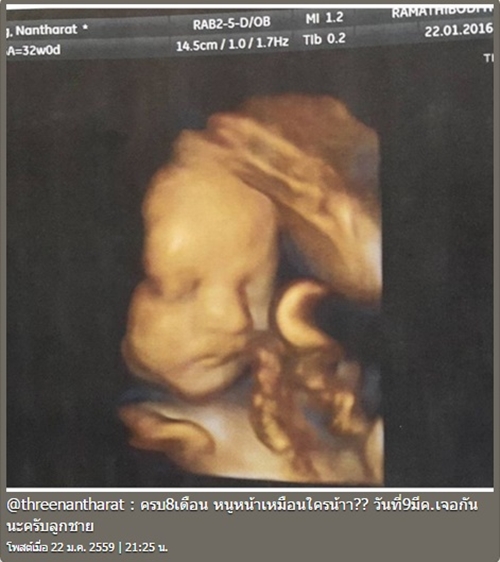

ล่าสุด (12 กุมภาพันธ์ 2559) สาวตรี นันทรัตน์ ก็ได้ออกมาเผยข่าวดีอีกครั้งพร้อมกับโพสต์ภาพอัลตราซาวด์ของลูกชายตัวน้อย ที่กำลังจะลืมตาดูโลกในวันที่ 9 มีนาคมนี้ ลงในอินสตาแกรมส่วนตัว แถมงานนี้ทั้งสาวตรี นันทรัตน์ และสามี เบิ่ง ทวีศักดิ์ เก็บอาการตื่นเต้นไม่ได้ เพราะทั้งคู่ต่างลงรูปเสื้อผ้าของลูกชายตัวน้อยแบบจัดเต็มหลายชุดทีเดียว ท่ามกลางแฟนคลับที่มาให้กำลังใจกันอย่างมากมาย

ภาพจาก Instagram threenantharat